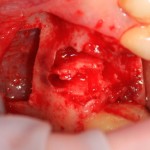

Немедленная имплантация — оптимальное решение в любой клинической ситуации